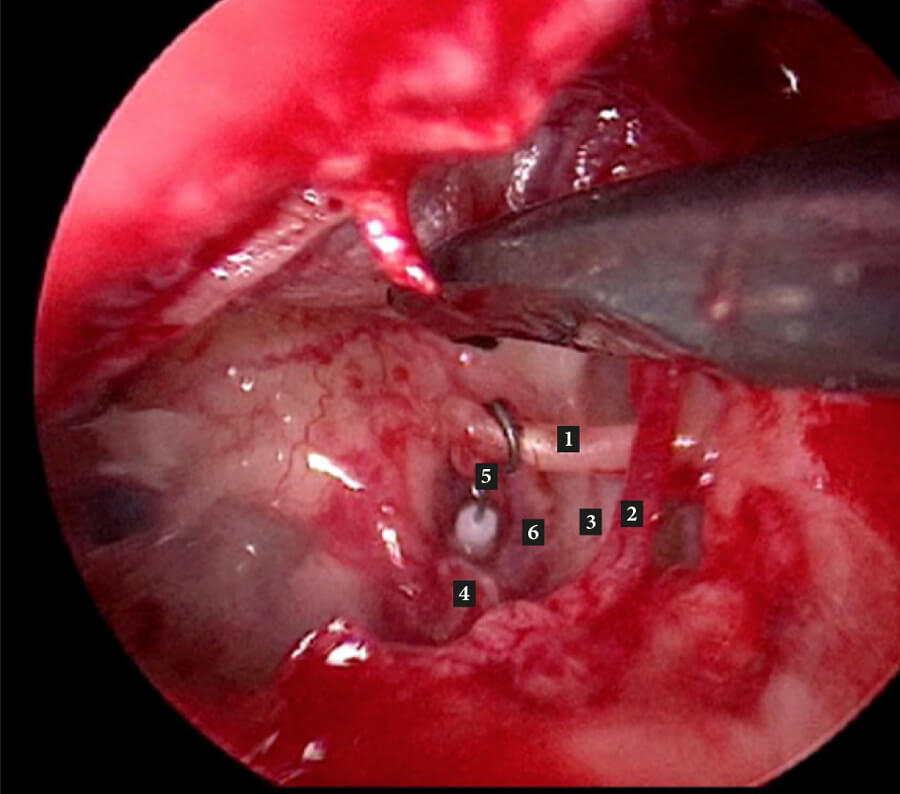

Figure C. Left middle ear with stapes piston in place. 1. Long process of incus; 2. Chorda tympani;

3. Tympanic segment facial nerve; 4. Pyramid 5. SMART Gyrus (self-crimping) stapes piston; 6. Oval window.